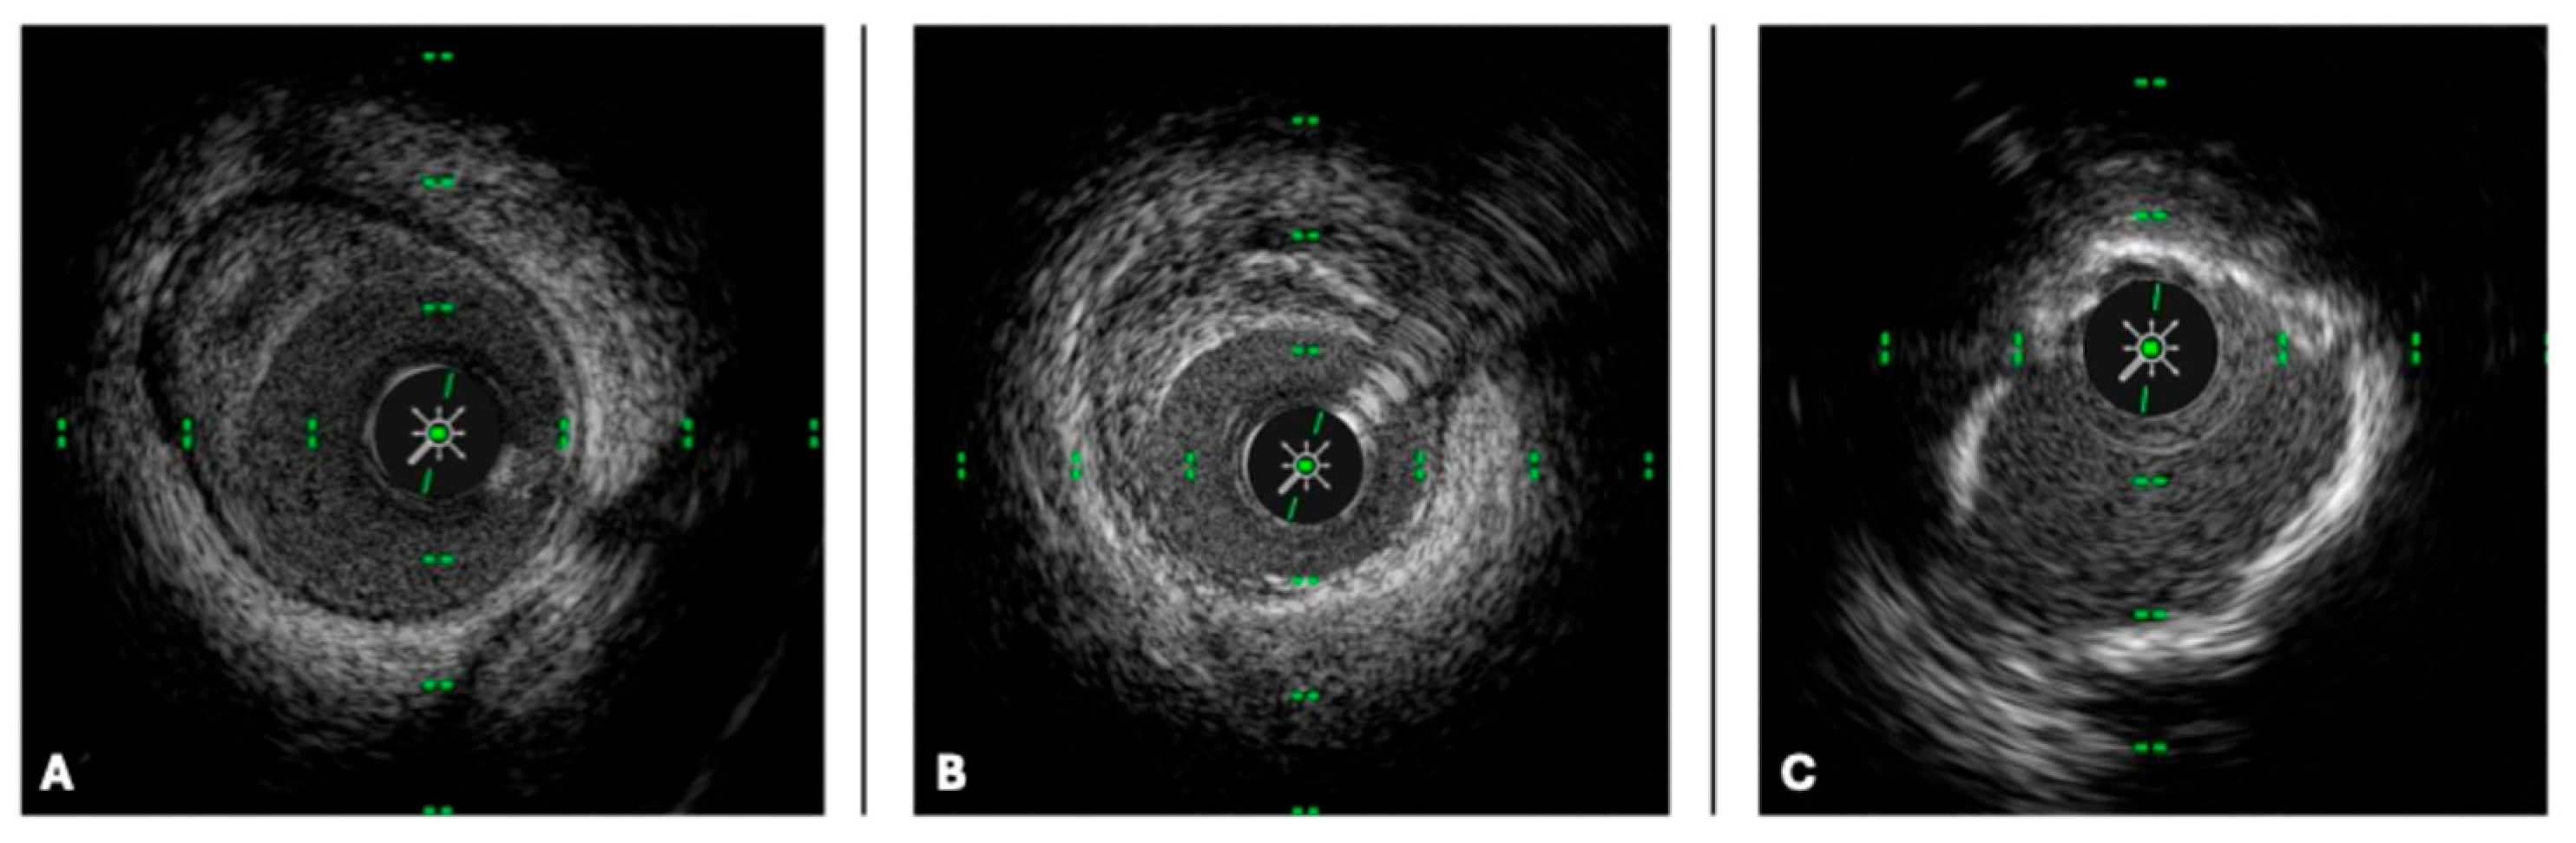

1. Introduction

2. Intravascular Imaging Technology

2.1. IVUS Technology

2.2. OCT Technology